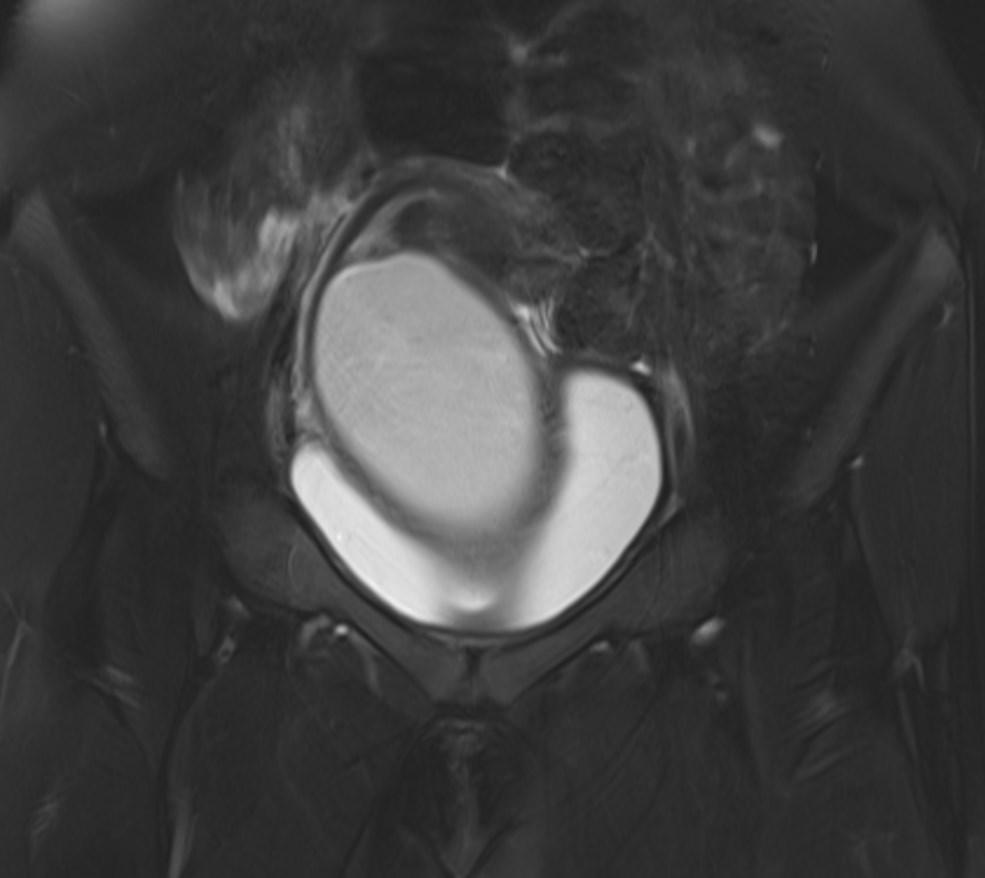

MR images showed hemorrhagic fluid in a distended vagina. The uterine cavity is not dilated.

In haematocolpos, there is accumulation of menstrual blood in the vagina in the setting of an anatomical obstruction, usually an imperforate hymen. When there is concurrent uterine distention, the term haematometrocolpos is used.